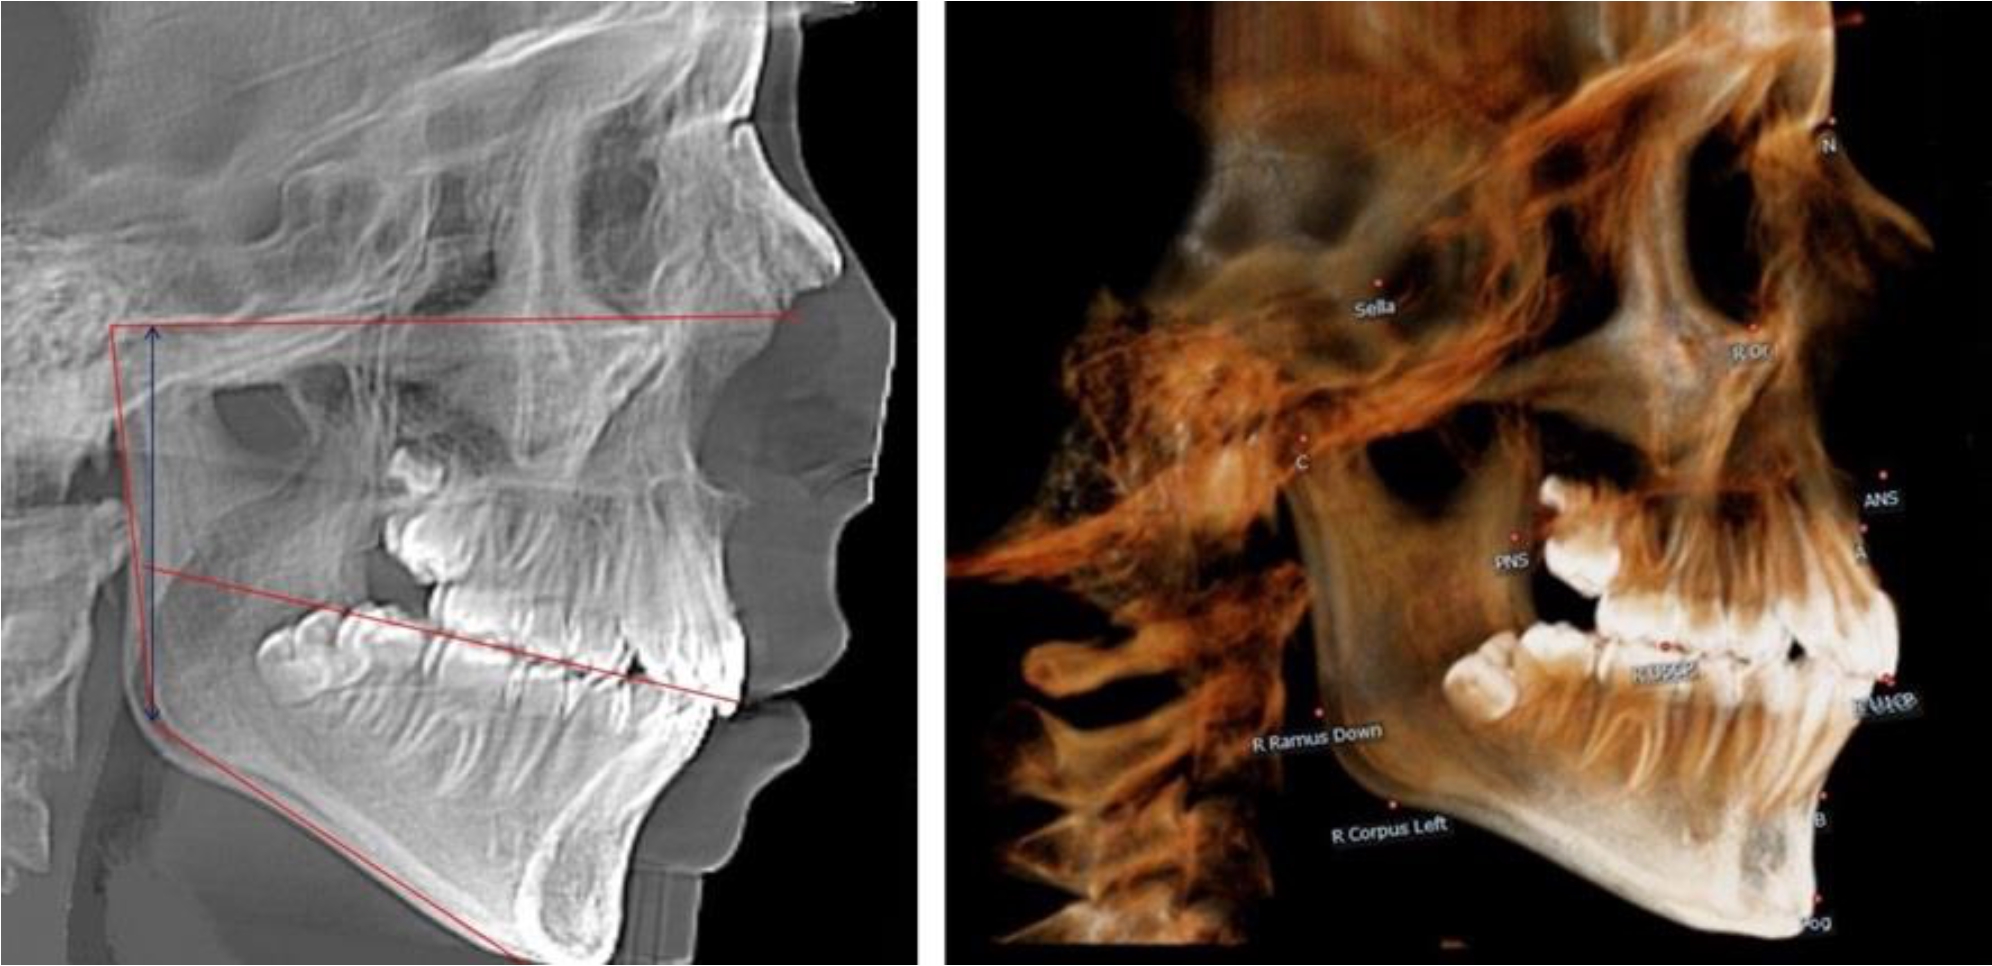

В 3-й группе были проанализированы 9 телерентгенограмм и 9 ортопантомограмм, что составило (8,49 ± 2,71) % от числа изученных рентгенограмм (рис. 3).

Рис. 3. ТРГ и ОПТГ пациента после смены молочных резцов

На всех рентгенограммах произошла смена молочных резцов постоянными. Окклюзионная линия делила ветвь на два отдела.

Высота ветви у детей у детей 3-й группы составляла (51,07 ± 2,72) мм, что было достоверно больше, чем у детей 1-й группы (р ˂ 0,05). При этом высота верхней окклюзионно-суставной части была (29,06 ± 1,44) мм, а нижней – (22,01 ± 1,59) мм. Высота верхней части была больше нижней, что и определяло особенности соразмерности частей ветви нижней челюсти в анализируемый возрастной период.

Относительные показатели соразмерности частей ветви нижней челюсти показали, что отношение высоты верхней части ветви к нижней в среднем составляло 1,32 ± 0,14. Отношение общей высоты ветви к верхней ее части составляло 1,75 ± 0,12, а отношение общей высоты ветви к нижней ее части было 2,32 ± 0,17, что и определяло особенности соразмерности частей ветви нижней челюсти в анализируемый возрастной период.